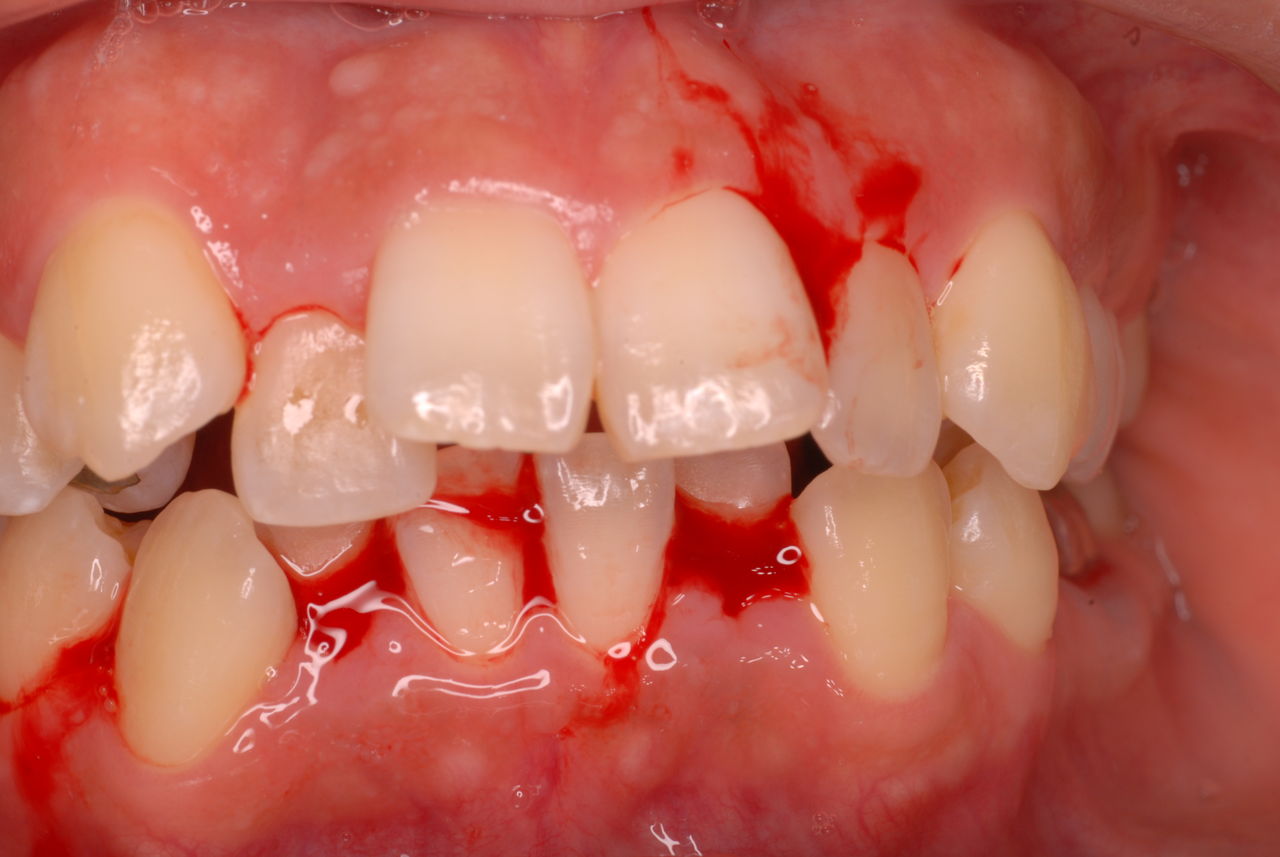

写真左下の親知らずが痛くなり抜歯しました。その後歯茎を除去して虫歯を露出させる処置を二回ほどしています。

レントゲンでは小さいですが、こう言う虫歯が一番怖いのです。

治療の成功率は極めて悪くすぐ再発しやすいのです。